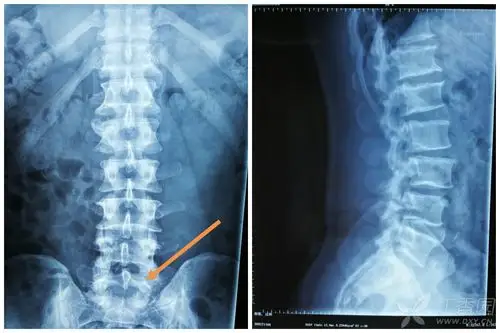

我这个属于骶骨隐裂么?

今天去拍x线,诊断为骶骨隐性裂,而且我问了两个骨科医师,他们看片后

隐性脊柱裂

Ⅱ度骶椎隐裂